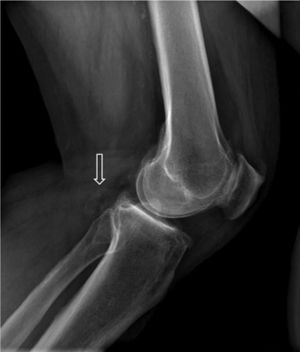

A male, 67 years of age, obese, with high blood pressure and dyslipidemia presented at the emergency department due to pain, cold and functional impairment of his lower left limb of 24-h onset. During anamnesis, the patient stated he had had a chronic intermittent pain in his left knee for a long time. A previous simple knee X-ray showed an osteochondroma (Fig. 1). The patient presented with a femoral pulse but with no popliteal and distal pulses. Artery examination was normal in the contralateral extremity. A CT angiogram was requested for the lower limbs which showed thrombosis of the popliteal artery adjacent to the osteochondroma (Figs. 2 and 3). We decided to perform in situ revascularization with femoro-popliteal saphenous vein graft (Fig. 4) avoiding the tunneling technique for anatomical positioning. To date, after 3 years of follow-up with eco-Doppler, the bypass continues maintaining permeability with ankle-arm index of 0.9, and no signs of popliteal vein injury.

Osteochondroma is the most common pseudotumoral bone lesion. The radiologic pathognomonic characteristic of this tumor is the cortical and medullar continuity of the lesions with the bone from which they protrude.1 They may be single or multiple.2 Some of the most common complications are the presence of bone deformity, fractures,1 vascular compromise3 and neurological compromise,4 formation of a bursa5 and malignant degeneration.6 Diagnosis may be made with an X-ray, although other imaging methods such as a scan, CT and MR may be used in suspected cases when symptoms occur or are in unusual locations.1 Vascular compromise may be caused by displacement of blood vessels (arteries and veins), by stenosis, occlusion and the formation of pseudoaneurisms, with the latter being more frequent at knee level,7 involving the popliteal artery or being presented as arterial thrombosis,8,9 as in this clinical case. Its presentation as thoracic outlet syndrome in the case of rib lesions has been described.10